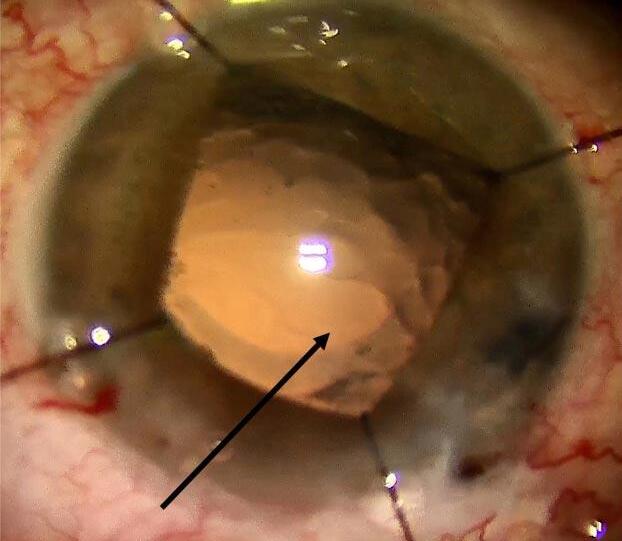

Existen RCP que son evidentemente irregulares y con bordes discontinuos, pero también nos podemos encontrar con una apertura aparentemente circular (Imagen 3) , sobre todo cuando la rotura sucedió con súbitos colapsos en la cámara anterior y la cápsula entra en contacto brevemente con el tip del faco o de la bomba de aspiración. Incluso en esta situación no nos debemos fiar de la continuidad, ya que puede haber microdesgarros en el borde que extiendan la apertura en las maniobras subsiguientes.

Imagen 3.